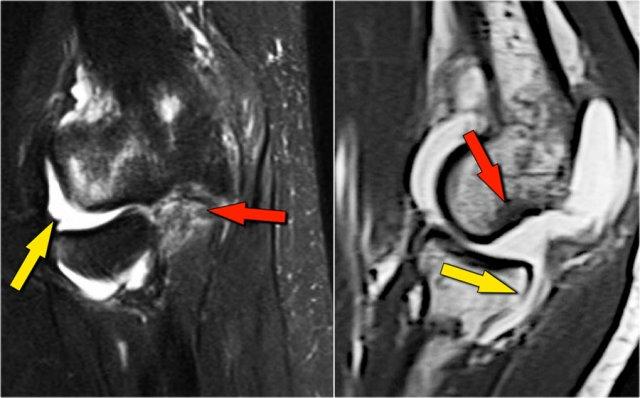

Đây là hình ảnh MRI.

Coronal view:

- Dây chằng bên ngoài bị bóc tách hoàn toàn (mũi tên vàng).

- radial head is subluxed.

- phù tủy xương của mỏm vẹt do gãy xương (mũi tên đỏ).

Sagittal view:

- Chỏm xương quay bị bán trật nhẹ ra phía sau (mũi tên vàng).

- Large effusion and capsular disruption posteriorly.

- Đụng dập mặt sau của chỏm con do va chạm với mỏm vẹt (mũi tên đỏ).

All these signs are the result of a posterior dislocation.